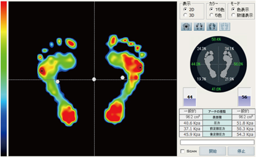

静止立位検査

プレートに両足肩幅で乗り、足底圧力の分布状態を検査をします。

検査時間内の平均圧力データを静止画として表示します。

基本画面

圧力分布の色分け表示や前後左右バランスを%表示します。

接地状態を分析しアーチの種類の確認も行えます。